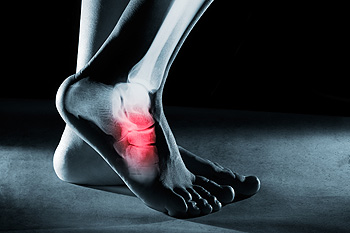

Common Foot Surgeries

Common Foot SurgeriesFoot pain can often be attributed to a number of conditions, including bunions, hammertoe, metatarsalgia, and neuromas, that require surgical intervention. Bunions are painful bony bumps on the side of the foot, caused by misalignment of the toe...